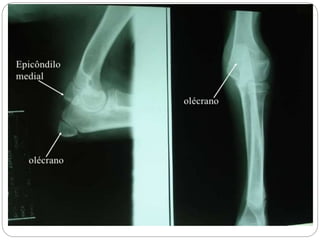

Cervicais (7) C1a C7 Toráxicas (13) T1 a T13 Lombares (7) L1 a L7 Sacras (3) São unidas e formam o osso Sacro Coccigeas (13 a 21) Co1 a Co13 ou Co21 formam a cauda Costelas (13 pares) 9 chamadas de verdadeiras e 4 de flutuantes Esqueleto apendicular Membro Anterior Escápula Úmero (braço) Rádio (antebraço) Carpo (joelho) Metacarpo (canela) Falanges (dedos) Membro posterior (pélvico) Coxal (Ísquio, Íleo e Púbis) (bacia) Fêmur (coxa) Paleta (rótula) Tíbia (perna) Perônio (perna) Tarso (jarrete) Metatarso (canela) Falanges (dedos)